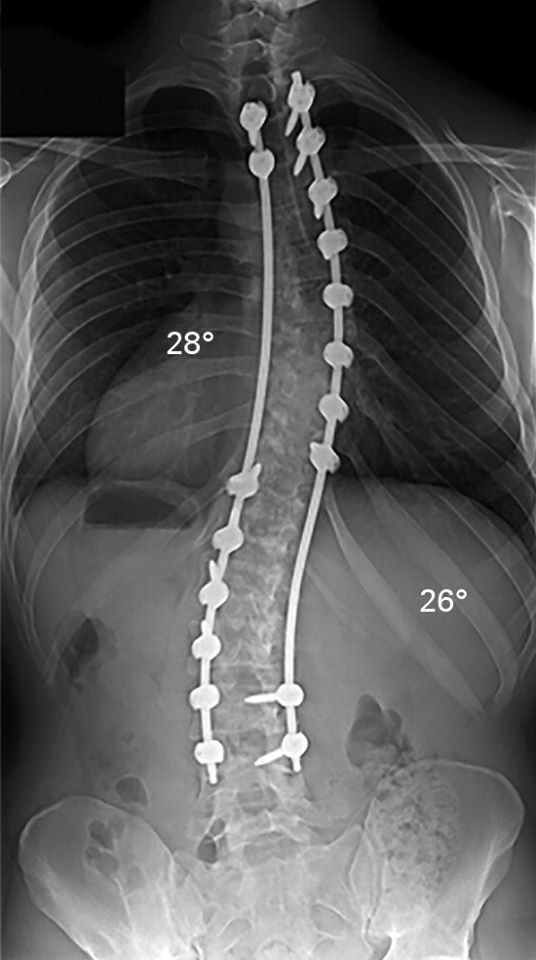

La escoliosis idiopática del adolescente (AIS) es una deformidad 3D compleja de la columna vertebral. Su prevalencia es de entre 2% y 3% en la población general, con casi el 10% de los pacientes que requieren algún tipo de tratamiento y hasta el 0,1% sometidos a cirugía. El aspecto cosmético de la deformidad es la mayor preocupación para el paciente y a menudo se acompaña de angustia psicosocial. Además, las curvas severas pueden causar angustia cardiopulmonar. Con beneficios comprobados de la cirugía, los objetivos del tratamiento son mejorar los resultados cosméticos y funcionales. Obtener la corrección en el plano coronal ya no es el único punto final importante. Con una mejor comprensión de la biomecánica espinal y los efectos a largo plazo del desequilibrio multiplanar, ahora sabemos que el equilibrio sagital es igualmente importante, si no más. Una mejor corrección de las deformidades también ha sido facilitada por una mejora en el diseño de implantes y una mejor comprensión de la metalurgia. Comprender el carácter único de cada deformidad es importante. Además, es importante utilizar el implante más apropiado y aplicar todos los principios de corrección a medida para lograr una corrección óptima. En este artículo, revisamos los conceptos actuales en cirugía AIS.